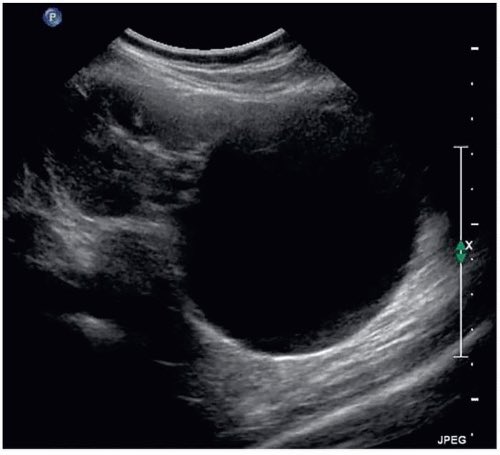

الاسباب :

غير معروفة ، الاصابة بارتفاع ضغط الدم ، قصور وظائف الكلى ، التقدم بالسن ، وفي حالات محدودة تكون باسباب وراثية او التهابات فطرية.

الاعراض : في الغالب بدون اعراض ، الم متقطع بالخاصرة او الجنب ، وفي حالات متقدمة ونادرة قد يكون دم بالبول